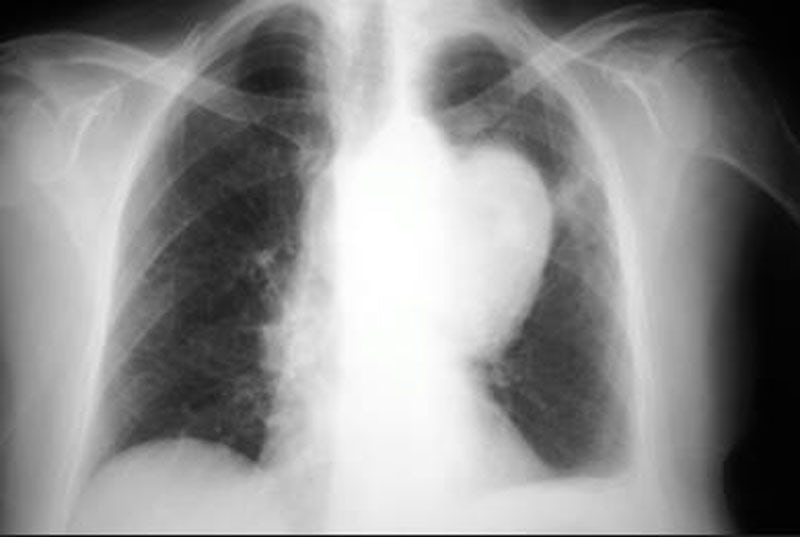

When Jonno Boyer-Dry was diagnosed with Hodgkin’s Lymphoma in 2014, he says it felt like he was the first patient to ever be diagnosed with cancer. He’d had a severe cough for four months, waking up in bed to feel like he was “drowning” as he gasped for air. His doctor gave him antibiotics and told him he had nothing to worry about—that he could, as planned, fly across the country to propose to his soon-to-be-wife on a mountaintop in the Adirondacks. He was wrong.

Boyer-Dry, 28 at the time, got back from his trip, ready to start his new life: he and his girlfriend had just graduated UPenn Law and moved across the country to Los Angeles for new jobs. But his cough persisted. He soon found out he had Stage 4 cancer, after another misdiagnosis in which a pulmonologist told him he did, in fact, have cancer but it was definitely “early stage.”

The majority of patients with Hodgkin’s Lymphoma are cured following their first round of chemotherapy, but Boyer-Dry wasn’t in the majority. He found out his first day back full-time at his new job that his condition had gotten significantly worse and that, if he wanted to live, he’d need to go through one of the most intense chemotherapy regimens available: in-patient chemo every three weeks for five days. Following this, he would then need to undergo a stem cell transplant which would wipe out his immune system. And, on top of all of that, he had to sign an agreement before going into surgery that he wouldn’t use cannabis in the hospital to help with the pain or nausea. His doctors were concerned it would be contaminated.